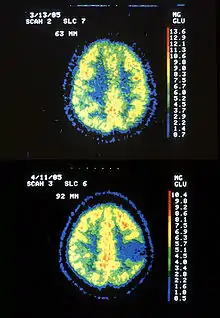

| Two PET images—the upper of which shows a normal brain and the lower shows astrocytoma. | |